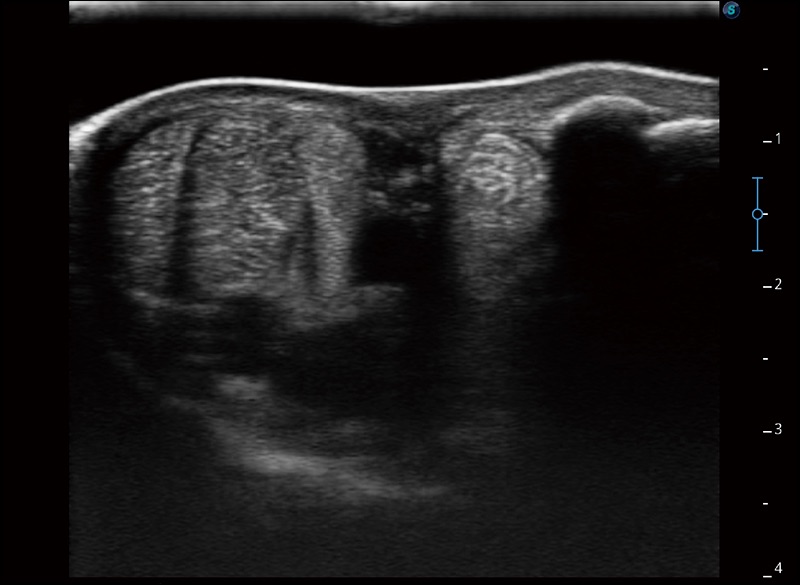

精致轻巧 性能迅捷

α1卓越的图像质量和便捷的工作流程,使每位宠物医生都能轻松扫查。其全面的兽用应用功能和紧凑型的结构设计,可以满足动物检查的多种需要。专业的预设检查模式和多领域测量软件包有助于为不同类型的动物提供检查, 让宠物医生能够出色的完成工作。